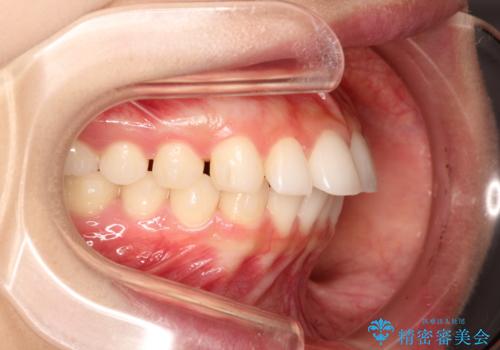

出っ歯の矯正治療 歯を抜かずにインビザラインで

- インビザラインで出っ歯を治したいとの希望がありました。

上顎の歯を全体的に後方に移動させて前歯を引っ込める計画としました。

インビザラインで目立たずに、痛みも少なく矯正治療を終えることができ満足していただけました。